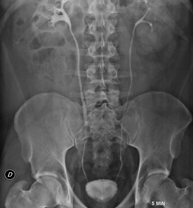

- RX Abdomen

Tècnica que usa els raigs X a través de la qual s'obtenen imatges de l'abdomen (estómac, intestí prim, intestí gros, fetge, ronyons, bufeta, pelvis òssia, etc.) per al seu estudi. - RX Columna lumbar

- Abdomen X-ray

An abdominal X-ray uses a small dose of radiation to obtain a two-dimensional image of the abdomen with its anatomical structures (stomach, small intestine, large intestine, liver, pancreas, kidneys, bladder, bony pelvis, etc.).